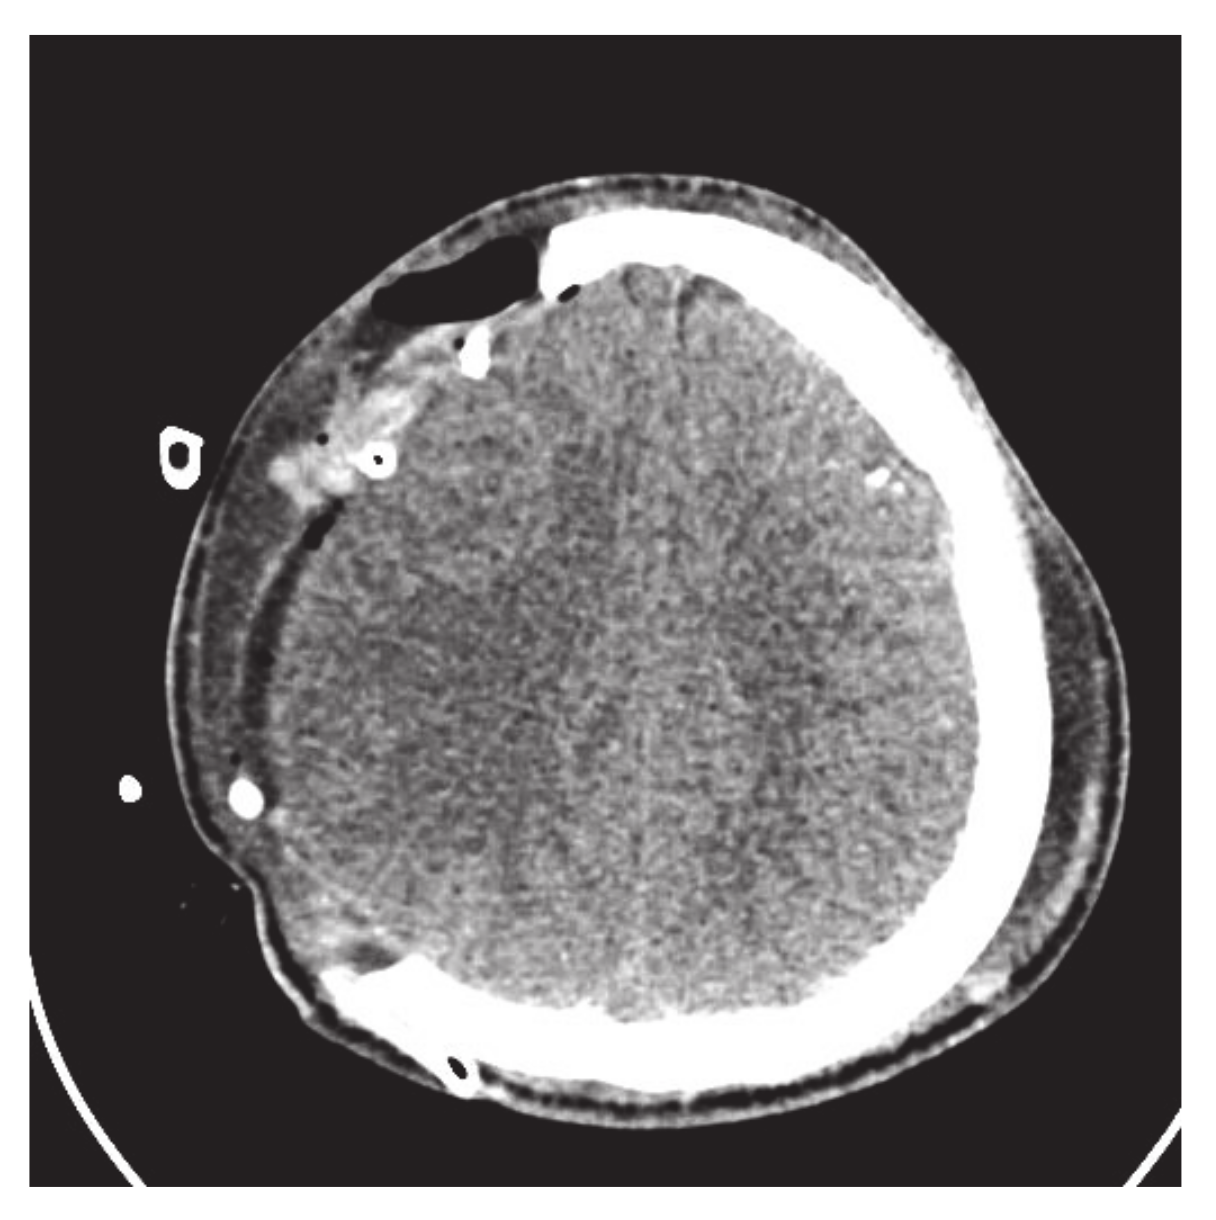

- Majeed, A.; Abbas, M.; Miura, K.T.; Kamran, M.; Nazir, T. Surface modeling from 2D contours with an application to craniofacial fracture construction. Mathematics 2020, 8, 1246. [Google Scholar] [CrossRef]

- Majeed, A.; Mt Piah, A.R.; Yahya, Z.R.; Abdullah, J.Y.; Rafique, M. Construction of occipital bone fracture using B-spline curves. Comput. Appl. Math. 2018, 37, 2877–2896. [Google Scholar] [CrossRef]

- Majeed, A.; Mt Piah, A.R.; Ridzuan, Y.Z. Surface Reconstruction from Parallel Curves with Application to Parietal Bone Fracture Reconstruction. PLoS ONE 2016, 11, e0149921. [Google Scholar] [CrossRef] [PubMed]

| 1 | Technical staff | Refs. [2,3] used CAD/CAM process for craniofacial fracture reconstruction. It required technical staff/tools, which causes low efficiency and high cost | In this method, no need for staff/tools, reconstruction is based on patient CT scan DICOM data |